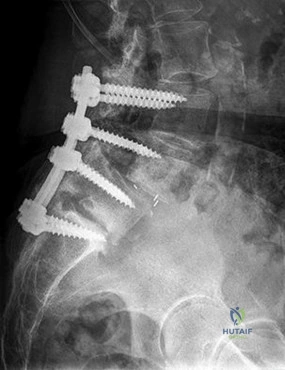

A 68-year-old male with a history of L3-S1 instrumented fusion presents with increasing back pain, progressive stooping posture, and difficulty ambulating. Clinical examination reveals a positive sagittal imbalance. A standing lateral spinopelvic radiograph is shown below.

Which radiographic parameter is MOST strongly correlated with functional outcome and satisfaction following surgical correction of adult spinal deformity with sagittal imbalance?

Option C (Posterior spinal fusion with instrumentation from T10-S1 with iliac fixation and an L4 pedicle subtraction osteotomy (PSO)) is the most appropriate choice. A PSO is a powerful osteotomy that allows for significant lordosis correction (typically 30-40 degrees at a single level). An L4 PSO is often chosen for its effectiveness in correcting lumbar kyphosis. Fusing from T10 to S1 with iliac fixation ensures that the entire affected segment is addressed, and distal fixation is robust enough to support the long construct and powerful correction. This comprehensive approach is necessary to achieve global sagittal balance and prevent distal junctional kyphosis.